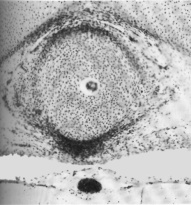

General view of eye

Retina